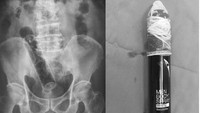

Pria 68 tahun mengaku rutin menggunakan kaleng hairspray untuk melancarkan BAB, tapi kali ini tersangkut di dalam rektum. Dokter berhasil mengeluarkannya tanpa komplikasi serius. (Foto: Malaysia Family Physician)